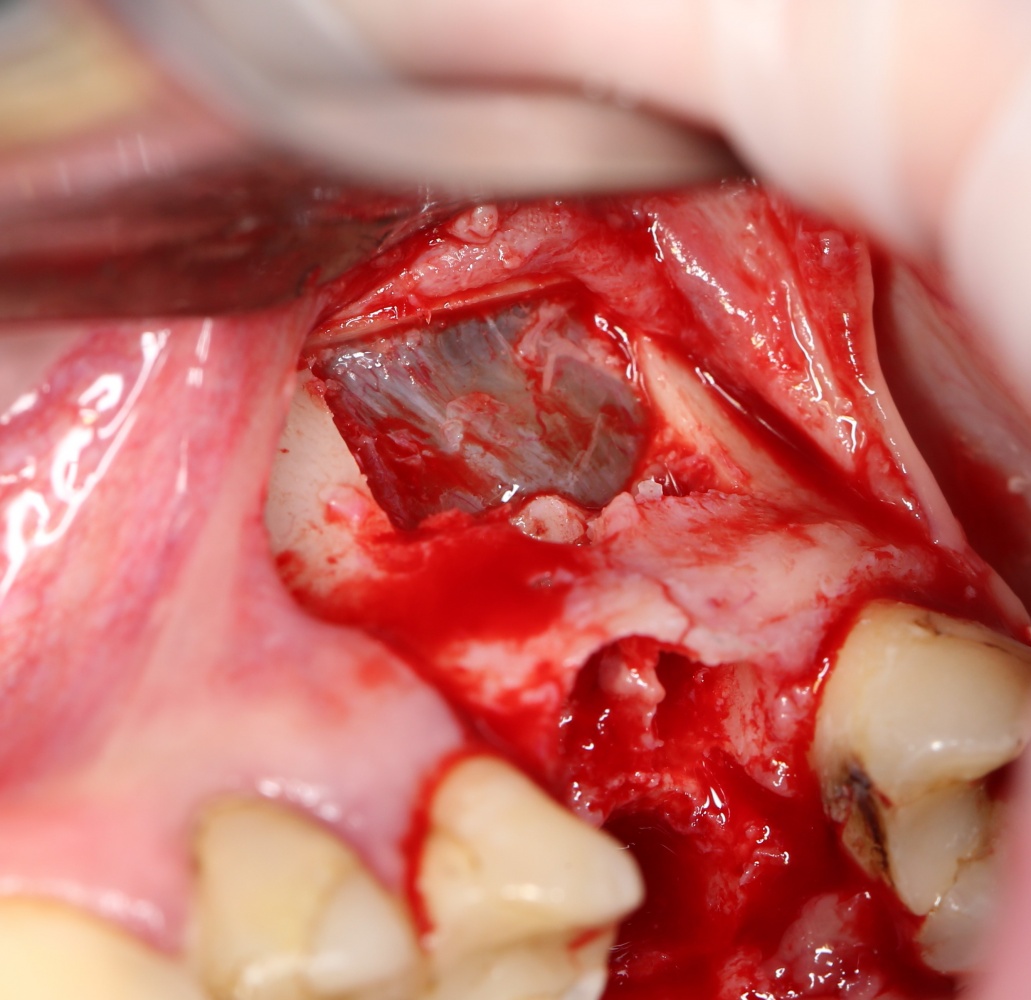

— образовавшимся при создании доступа костным фрагментом, при необходимости, можно закрыть даже большую перфорацию:

В контексте сегодняшней темы было бы важнее рассмотреть место и форму апертуры доступа.